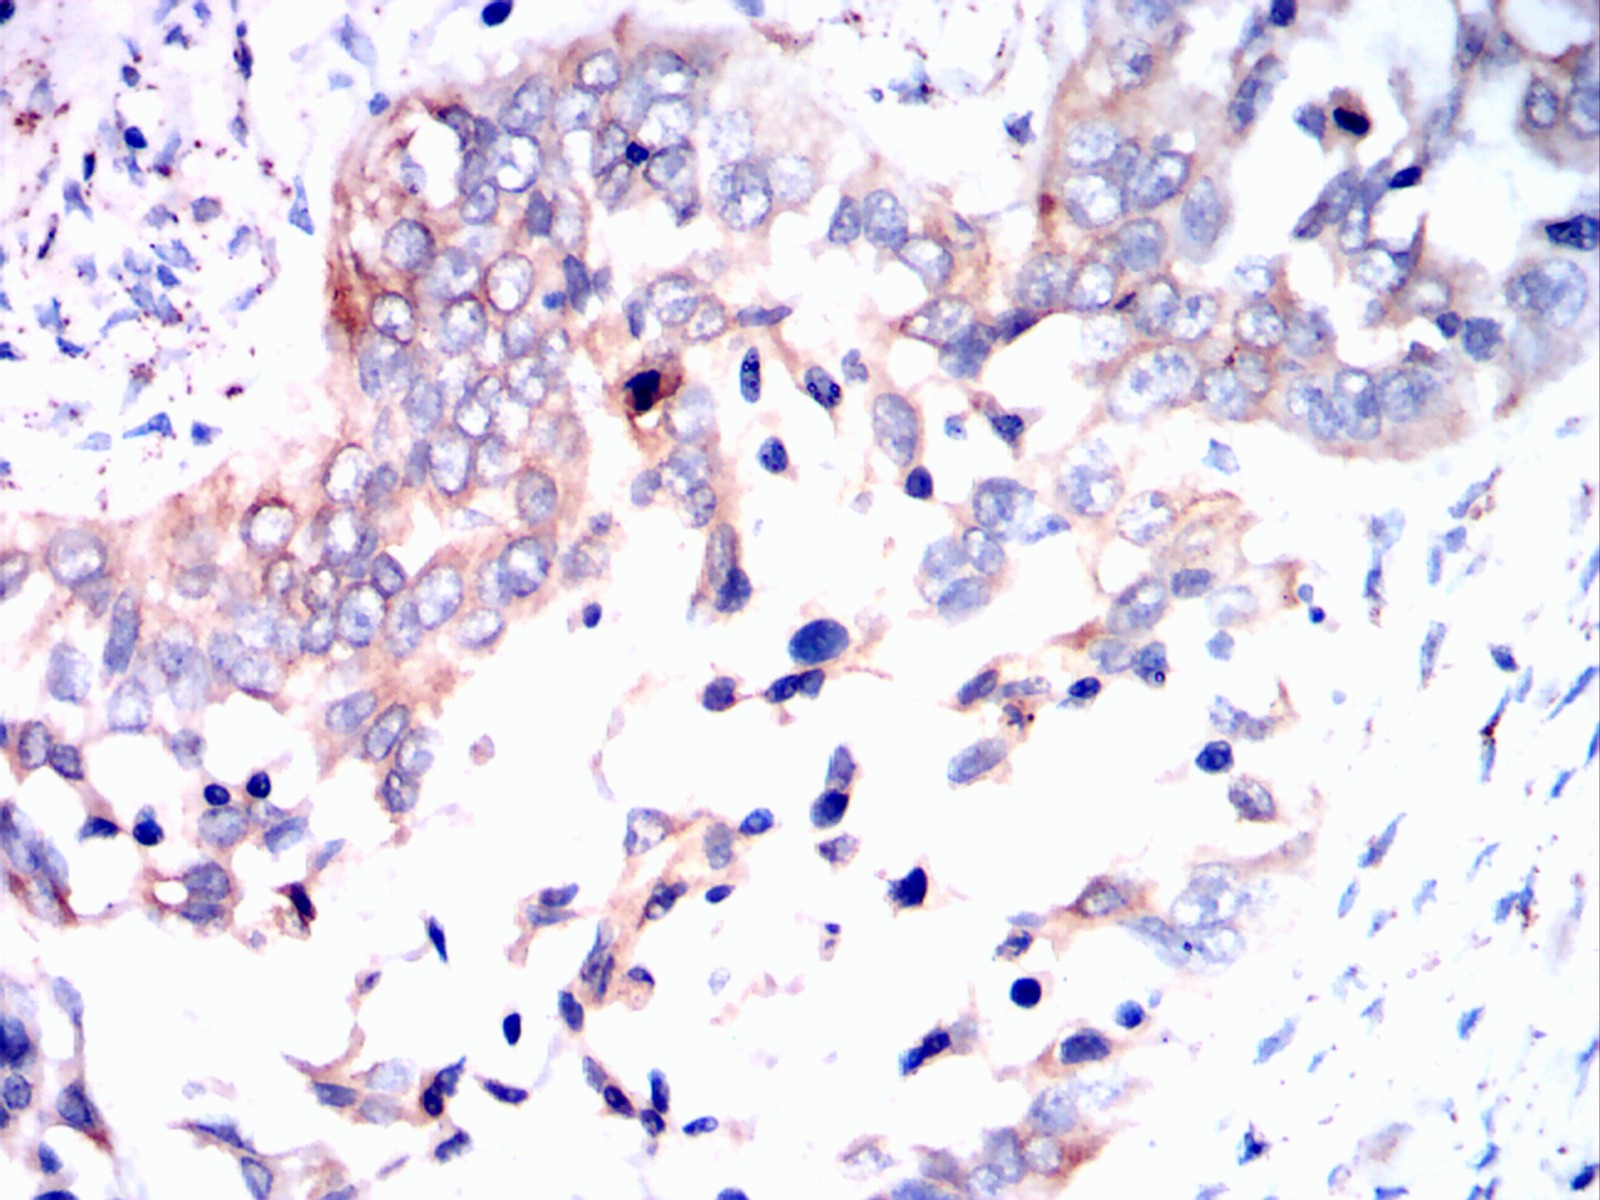

Immunohistochemical analysis of paraffin-embedded lung cancer tissues using ERBB3 mouse mAb with DAB staining.